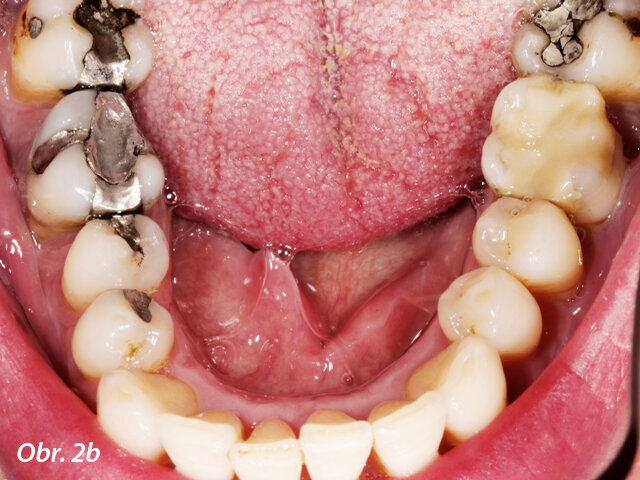

Pacient požadoval výměnu amalgámových výplní v horní (a) a dolní (b) čelisti za celokeramické náhrady.

Pacient si přál odstranit víceploškové amalgámové výplně v horní a dolní čelisti (obr. 2a, b) a nahradit je celokeramickými náhradami zhotovenými s co nejmenším úsilím. Jednalo se o částečné korunky. V distálním úseku horní čelisti byla indikována můstková náhrada vyrobená z lithium disilikátové keramiky. Všechny ostatní nepřímé náhrady měly být vyrobeny z materiálu n!ce. Materiál je biologicky kompatibilní a relativně pevný i bez dodatečného krystalizačního pálení, přičemž disponuje přirozenými světelně optickými vlastnostmi.